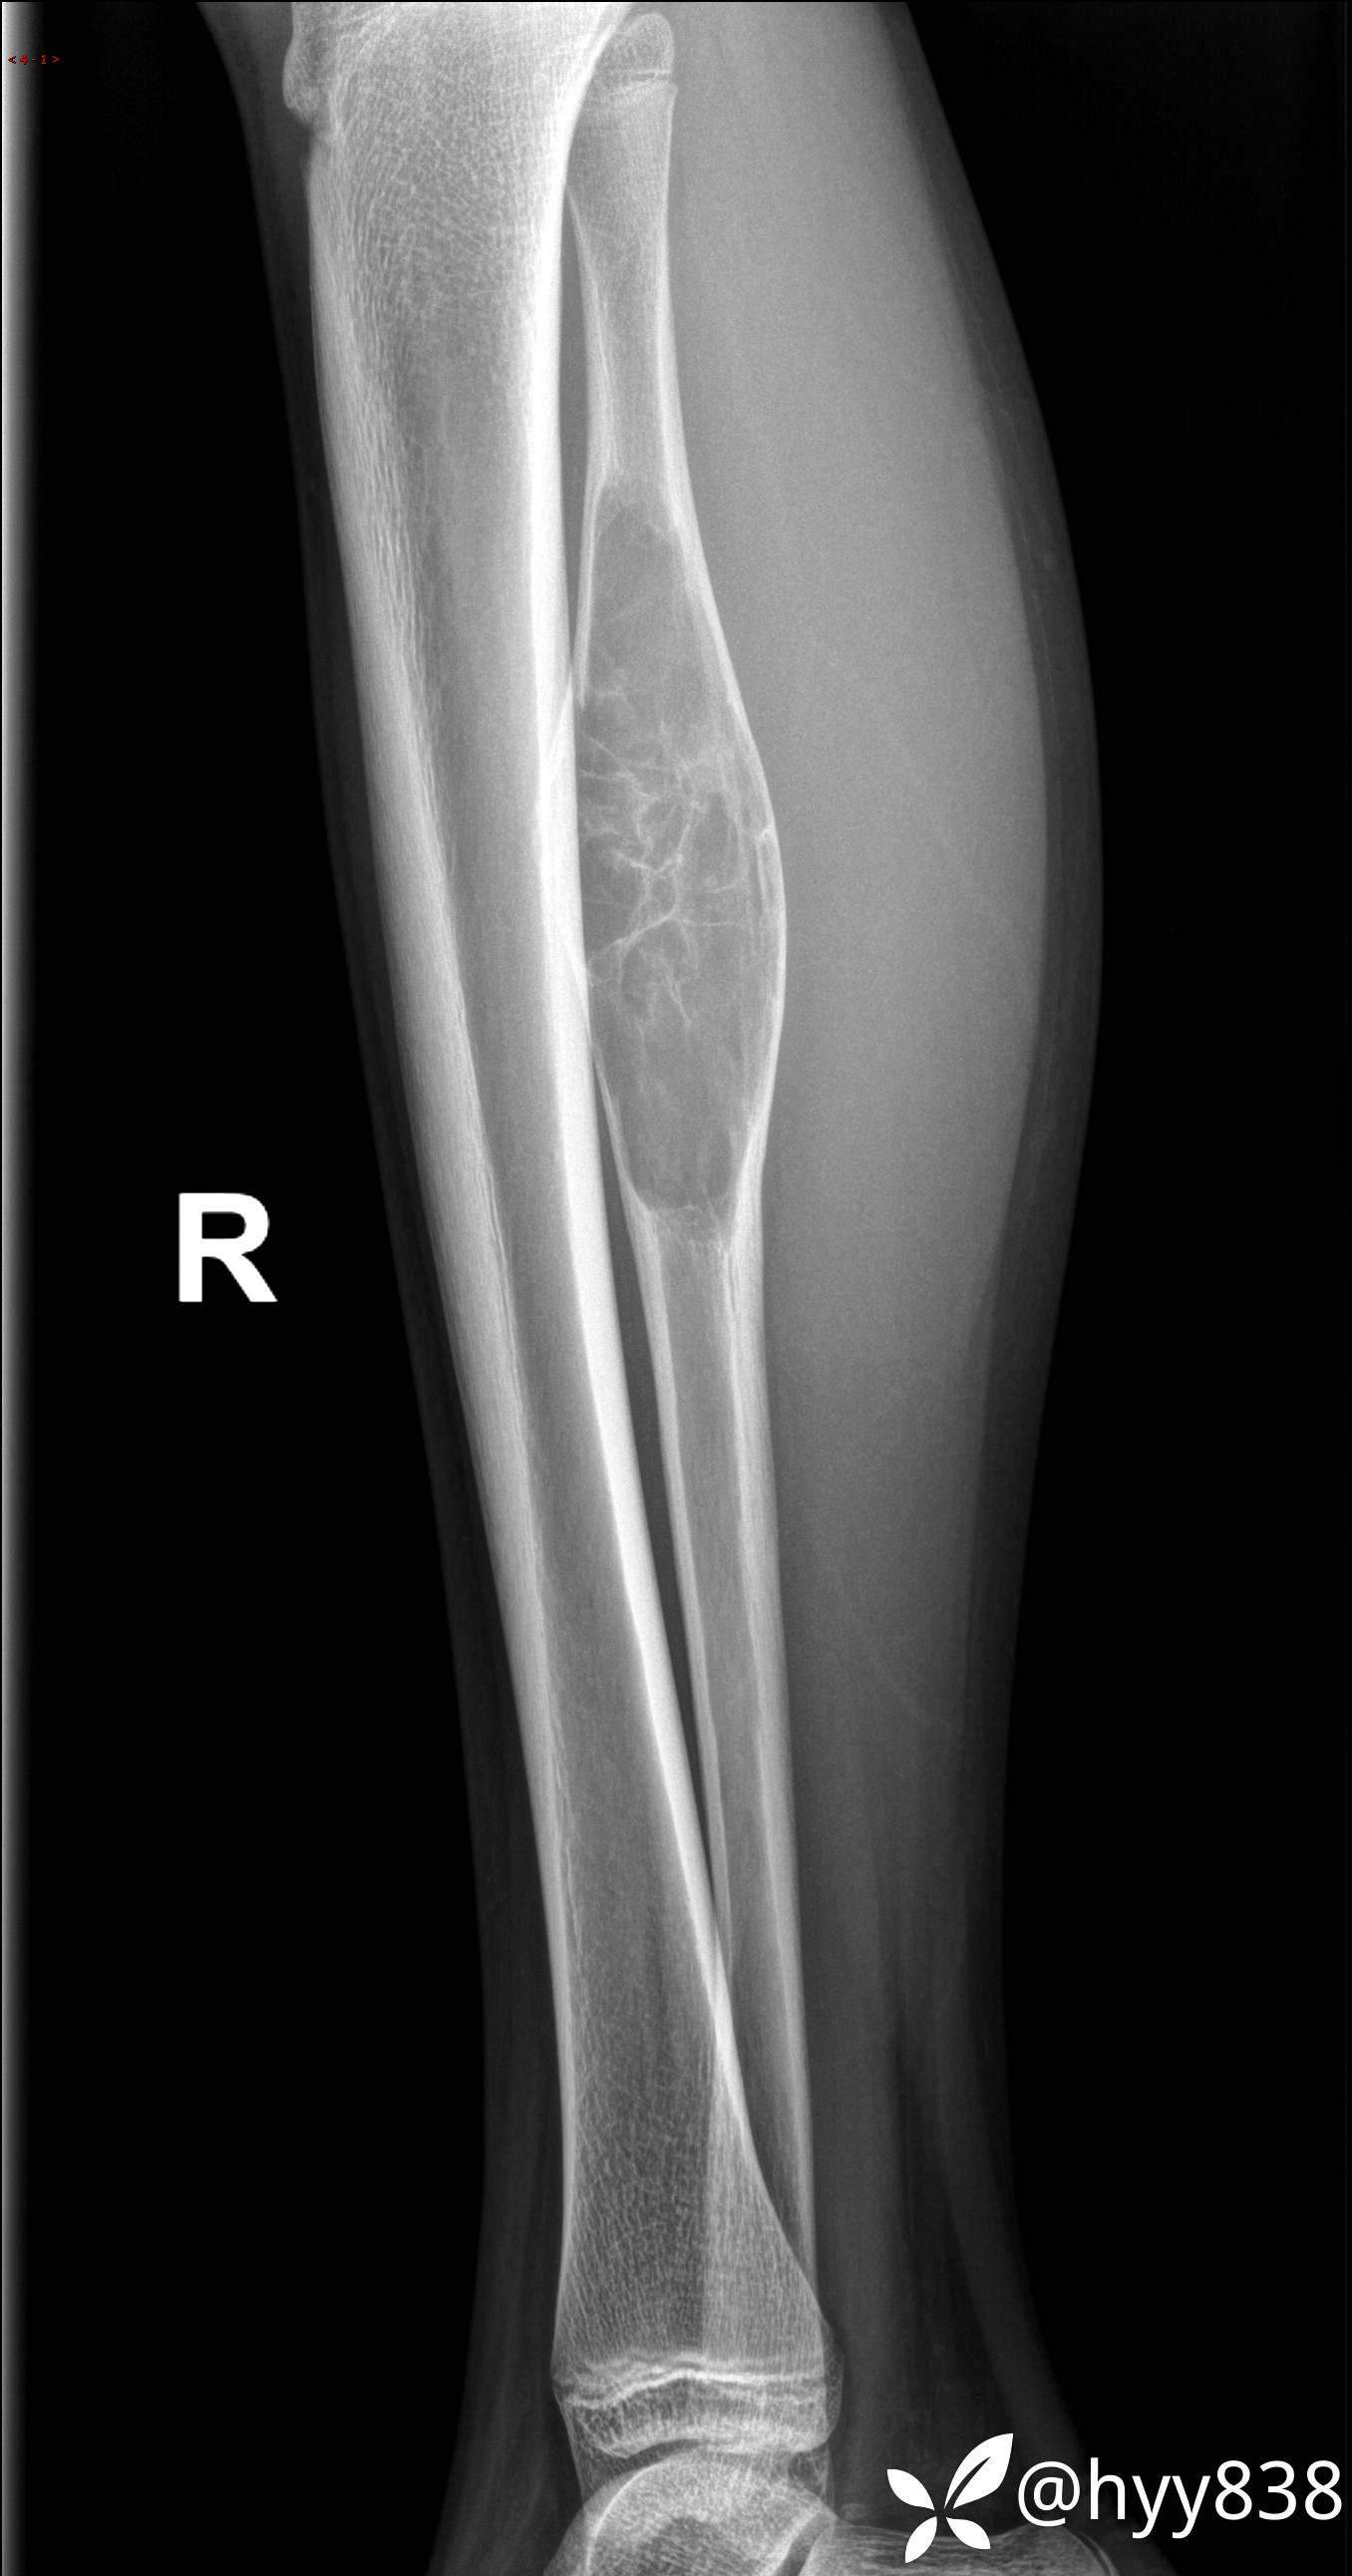

儿童,发现右小腿肿硬性肿物3年。资料齐全,ABC VS SBC VS FD--结果公布

主诉:发现右小腿肿硬性肿物3年

简要病史:患者3年前发现右小腿硬性肿物,按压稍疼痛,不伴活动受限及其他不适,后行胫腓骨MRI示:右腓骨上段肿物,考虑良性病变,现来院就诊,遂以“右下肢骨肿瘤”收入我科。 患者起病以来,精神良好,未进饮食,大小便正常,体重体力无明显改变。

临床诊断:胫骨肿物

平片